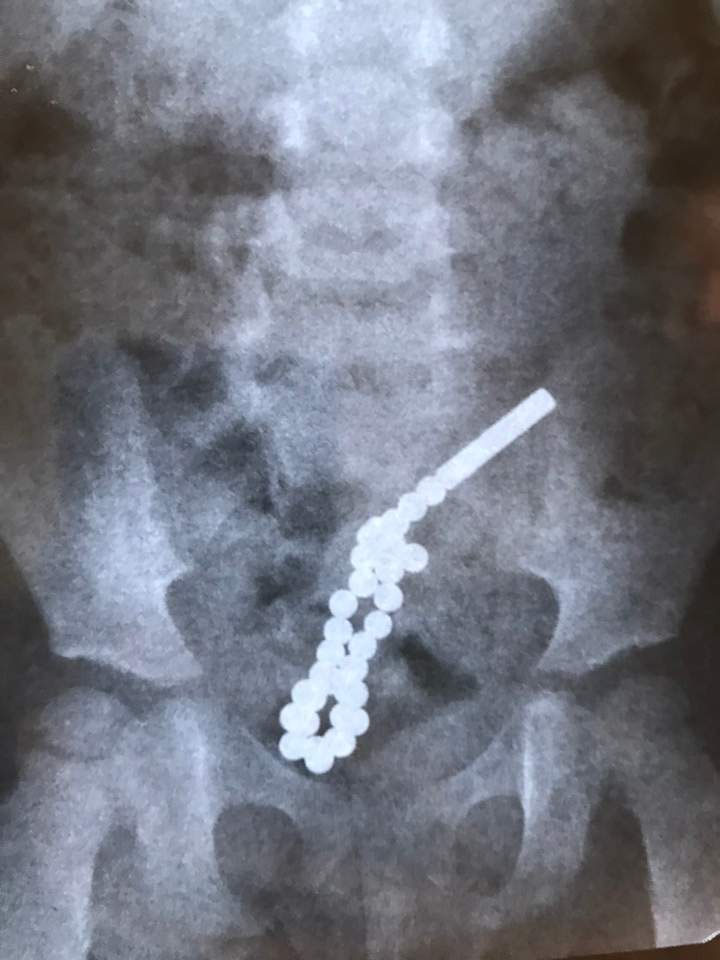

Львовские хирурги провели срочную операцию двухлетней девочке. Она умудрилась проглотить 31 намагниченный шарик.

Во Львове хирургам львовской городской детской больницы пришлось экстренно оперировать двухлетнюю девочку, проглотившую 30 сильно намагниченных шариков. Хирургическая операция по спасению ребенка продолжалась почти два часа, сообщает ZAXID.NET.

По словам детского хирурга Дмитрия Грицака, девочка поступила в больницу с жалобами на боль в животе. Рентген показал, что достать шарики было бы нереально, поэтому приходилось делать операцию традиционным способом — через разрез на животе.

«Эти неодимовые магнитики очень мощные. Ребенок проглотил 31 такой магнитный шарик. Часть из них попала в одну петлю кишечника, другая — в другую. В кишечнике они между собой соединились и пробили семь дыр в стенках кишечника», — рассказал Грицак.